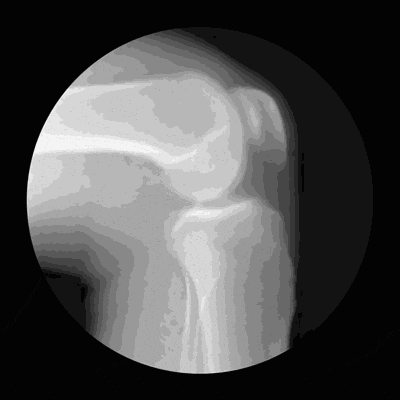

膝关节由股骨、胫骨和髌骨组成,股骨在上,胫骨在下,髌骨在表面。这三块骨头彼此对接的关节处,覆盖着一层脆弱的软骨,软骨最怕的是长时间处于压力状态。

如果膝关节长期处于压力状态,软骨的抗磨损能力就会下降,就会像图(1)这样出现软骨退化,甚至剥脱,从而诱发骨关节炎。

图(1)